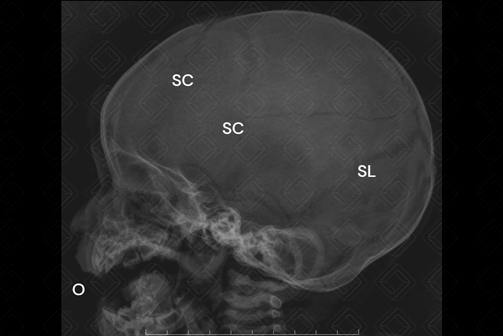

Radiografia de crânio AP e perfil (são as incidências padrões realizadas neste exame).

Legenda: SC = sutura coronal; SL = sutura lambdoide; O = órbita.